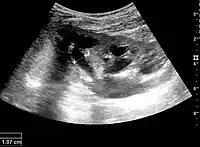

The kidney is divided into parenchyma and renal sinus. The renal sinus is hyperechoic and is composed of calyces, the renal pelvis, fat and the major intrarenal vessels. In the normal kidney, the urinary collecting system in the renal sinus is not visible, but it creates a heteroechoic appearance with the interposed fat and vessels. The parenchyma is more hypoechoic and homogenous and is divided into the outermost cortex and the innermost and slightly less echogenic medullary pyramids. Between the pyramids are the cortical infoldings, called columns of Bertin (Figure 1). In the pediatric patient, it is easier to differentiate the hypoechoic medullar pyramids from the more echogenic peripheral zone of the cortex in the parenchyma rim, as well as the columns of Bertin (Figure 2).[1]

Figure 1. Normal adult kidney. Measurement of kidney length on the US image is illustrated by ‘+’ and a dashed line. *Column of Bertin; ** pyramid; *** cortex; **** sinus.[1]